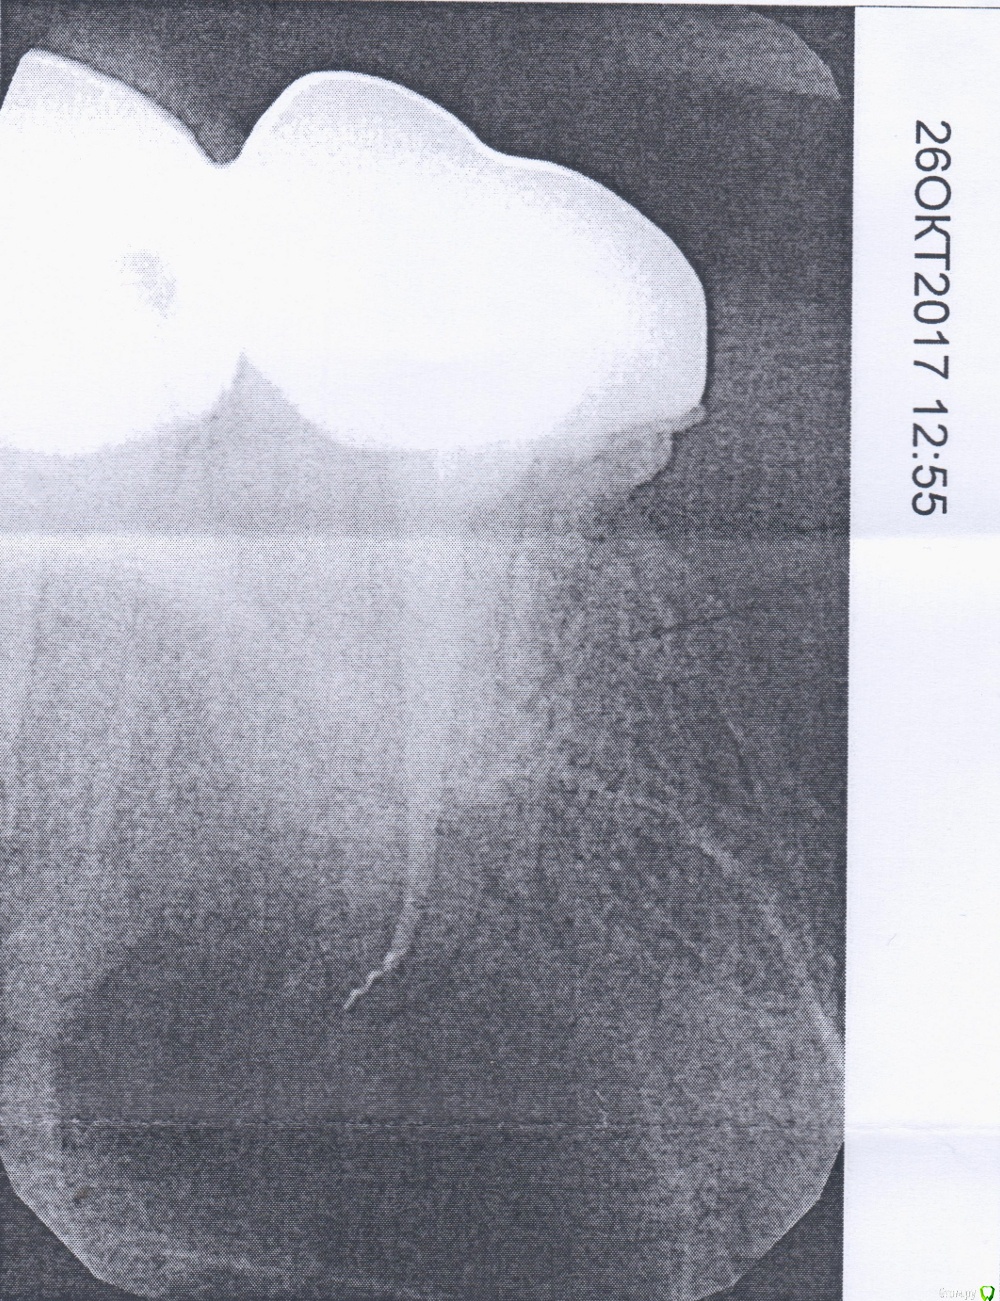

Татьяна.А Опубликовано 15 июня, 2018 Поделиться Опубликовано 15 июня, 2018 (изменено) Здравствуйте. Хотелось бы задать вопрос.Чуть больше года назад на 17 зуб поставили коронку. Позже он начал ныть. Сделала снимок. Он оказался слишком маленьким и ничего не показал. Сделала повторный снимок. И вот на нем уже стал заметен кусок инструмента. Стоматолог, который смотрел зуб, сказал, что в этом ничего страшного. Протезист тоже успокоил. Зуб перестал болеть и не беспокоил до недавнего времени. Сейчас зуб ноет и отдает в соседние (те тоже без нервов). Зуб мудрости удален. Десна нормальная, без каких-то признаков опухолей и свищей (если правильно назвала). Боль появляется, когда нажимаю на десну у корня.Прикладываю старый снимок, по которому и ставили диагноз. Изменено 15 июня, 2018 пользователем Татьяна.А Ссылка на комментарий

red_butler Опубликовано 15 июня, 2018 Поделиться Опубликовано 15 июня, 2018 к сожалению снимок не информативен, лучше сделать Кт Ссылка на комментарий